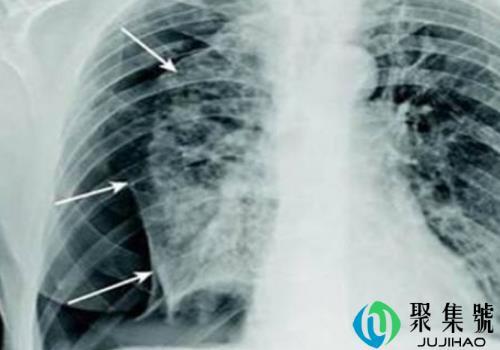

轻微气胸一般几天自愈气胸只要不严重是不会引起死亡的,发现气胸积极治疗就可以了,不用太紧张,那么轻微气胸一般几天自愈?为什么瘦的人容易气胸?气胸,很多人对这个病是不陌生的,是经常听说的吧!气胸的量是有一个期间范围的,只...